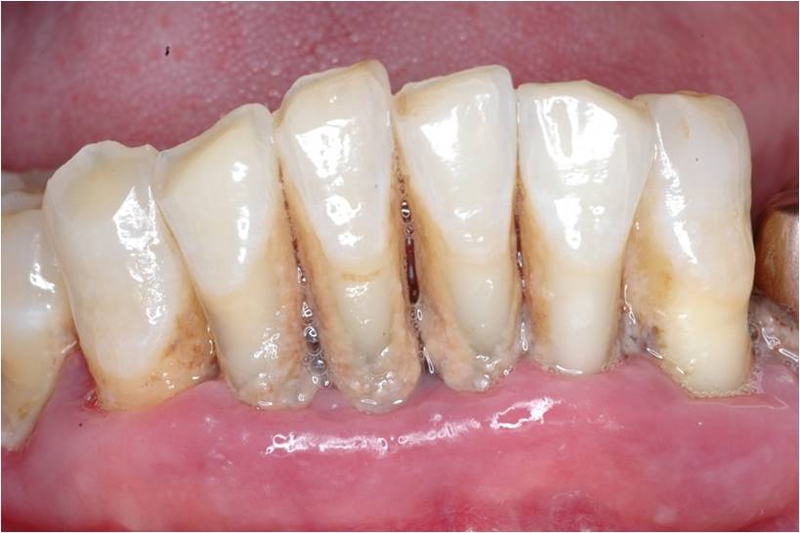

昨天,一位林博川醫師看了十幾年的患者來了。這十幾年來呢,該患者的口腔衛生都非常差。林博川醫師不厭其煩的在提醒這位患者刷牙的部分要加強加強再加強,但是這位患者不是刷得差而已唷,是非常非常差!那這次患者來的狀況是,全口的牙齦都又紅又腫,還佈滿了牙結石!!!

其實由上面這張環口片可以瞭解,患者有嚴重的牙周病,經林博川醫師的診斷,建議患者應將不可留的牙齒予以拔除,利用全口活動假牙或植牙的方式來重建。但是,患者堅持不考慮活動假牙,也不考慮植牙,患者只想保持現狀,試圖尋找他”想要”的治療方式。林博川醫師秉持著做為牙醫師多年的醫德與良知去告訴患者,若是患者想要擁有固定的牙齒,就必須只能是植牙而不是患者所想要的牙橋式的假牙了。